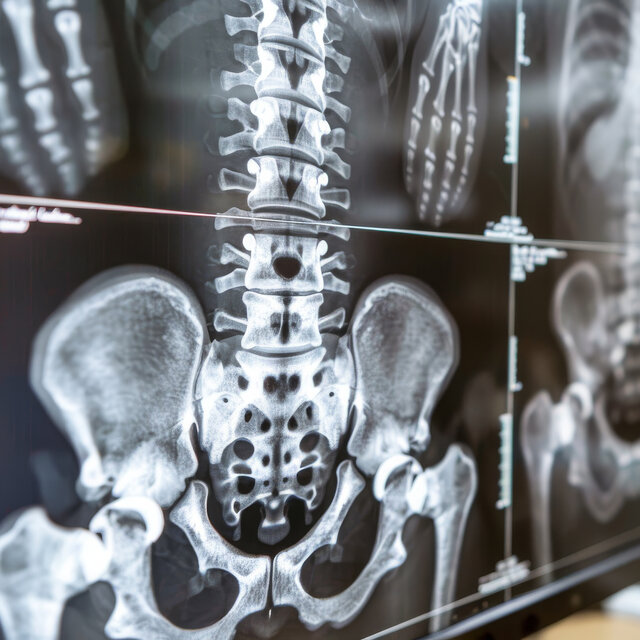

DIGITALES RÖNTGEN

Unsere Praxis verfügt über die neueste Technologie der digitalen Röntgendiagnostik. Damit wird die Strahlenbelastung des Patienten auf das Nötigste reduziert. Durch die digitale Nachbearbeitung sind die Bilder immer reproduzierbar und können digital an Patienten und Mitbehandler weitergegeben werden.